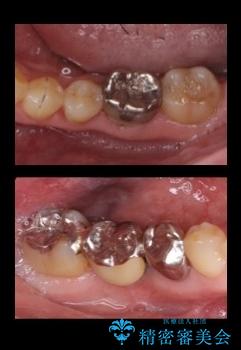

矯正治療後、右下のインレーブリッジおよび左下の銀歯のやりかえを行なっています。